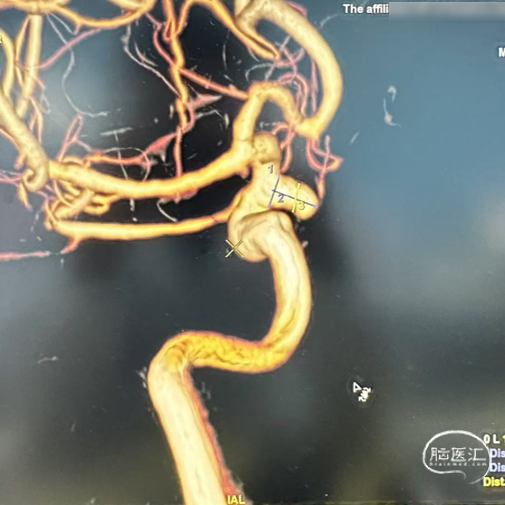

术前影像

左侧颈内动脉造影:左侧颈内动脉C6段动脉瘤。

左侧颈内动脉三维重建:左侧颈内动脉C6动脉瘤。

术前3D造影